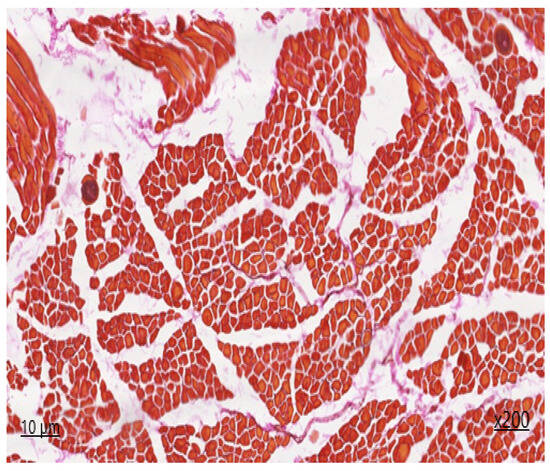

Upon histological examination of muscle sections from the heart (Figure 1 and Figure 2), it is evident that both longitudinal and partially transverse sections of muscle fibres are visible within the field of view. The ratio of muscle to adipose tissue is 90/1. Epimysium is not defined. The perimysium is of normal thickness and structure. The density of vessels is increased due to the presence of areas of neoangiogenesis and single nerve trunks. The density of endomysial slits is increased, containing a large number of capillary lumina and fibroblast nuclei, with areas of sprouting fibrous fibres. The sarcoplasm is slightly thickened, with muscle fibre nuclei located parallel to the periphery of the longitudinal line of the muscle fibre. The transverse striation in the unaffected muscle fibres is preserved, and the myoglobin saturation is sufficient. The diameter of the muscle fibre is 45 μm. On histological examination, the area of the lesion containing sarcocysts, predominantly of the second generation, is identified to be filled with endozoites, measuring 62 × 34 microns in size.

The affected muscle fibers display a lack of transverse striation, and the sarcoplasm forms an oval-shaped connective tissue capsule. On the periphery of the cyst capsule, non-specific inflammation is observed in the form of granulocytic infiltration with the presence of eosinophils. The degree of inflammation of the muscle tissue in the surrounding area is visualised in the form of serous reactive myositis of focal character.

Upon additional histochemical staining by Van Gizon, the fibrous fibers exhibited a bright crimson colouration, with an increased density due to concentric structures on the periphery of neurovascular bundles and due to thickening of perimysium fibers deeply embedded in endomysial spaces. The reaction of muscle fibers is greenish-brown, indicating the absence of fibrous tissue within the muscle fiber.

Figure 1. Sarcocystis in the cardiac tissue, first-generation staining with haematoxylin and eosin ×200.

Figure 2. Sarcocystis in the cardiac tissue, second-generation Van Gieson staining ×200.